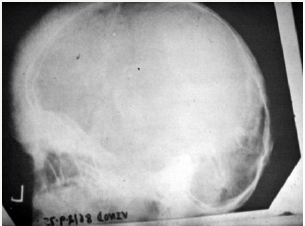

Figure 2: Postoperative.

c. Hairs on end: A patient with frequent headache and weakness was referred to the clinic and was diagnosed with enlarged spleen. On X-ray examination, as expected the skull showed outer margin lined by hair like projection (Figure 2) all along semicircular periphery of the skull. This is well documented text book affiliation with B (beta) thalassemia and a classical demonstration of multiple gene-interacting trait [8].